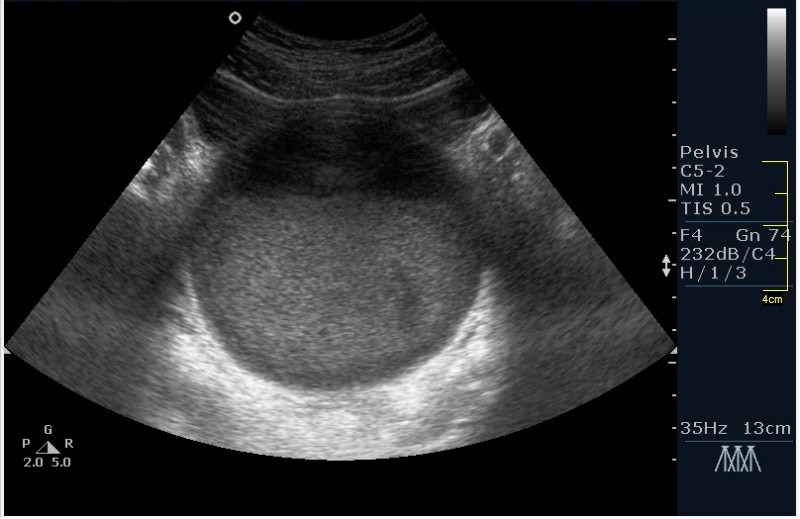

Девочка 12 лет; жалобы на частое мочеиспускание; тупые, тянущие боли в малом тазу. Менструацию отрицает. УЗИ малого таза, все сонограммы выполнены по средней линии, в поперечной и сагитальной проекциях.

Гематокольпос при заращении девственной плевы. Менархе. Врожденная аномалия половых органов.